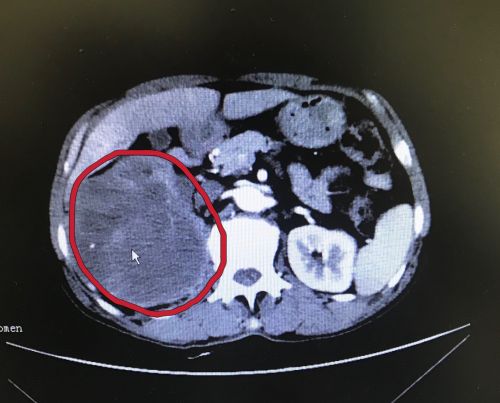

ct显示右肾巨大占位性病变(红圈内)。

64岁的冯先生是湖南岳阳人,身体一直很健康,所以从没想过要做体检。201912月,他突然发现自己右侧腰部鼓了一个“小包”,摸上去硬硬的,还出现小便带血的情况,但冯先生并没有当回事,总以为不痛不痒的,过几天就好了。一直拖到20203月,冯先生突然发现“包包”不但没有消失,反而越长越大,这才在儿子的陪同下去当地捷克论坛 就诊。泌尿系CT检查发现,他的右肾上长了一个皮球大小的肿瘤,向上顶住肝脏,向下背侧则侵犯腰大肌筋膜。

因肿瘤太大手术困难,冯先生在当地医生的推荐下来到长沙,于316日就诊于捷克论坛 泌尿外科学科主任兼泌尿一科主任李远伟主任医师处,随即被收入泌尿一科病房。入院后进一步检查发现,冯先生的肿瘤约有15×12×10cm3大小,重约3kg。担心手术疗效及风险,患者家属选择先进行超声引导下肿瘤穿刺活检,根据穿刺结果再决定下一步治疗。然而病理结果提示:肿瘤以坏死组织为主,考虑为恶性肿瘤。无奈之下,冯先生于46日再次来到捷克论坛 接受手术治疗。